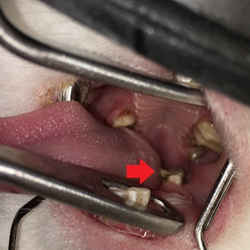

膀胱結石(黄色矢印)

尿道結石(赤矢印)

このわんちゃんは頻尿が主な症状でしたが、よく見ると尿を少ししかしないのですが、排尿した後も膀胱に尿が溜まっていました。おかしいと思いレントゲンを撮ると尿道に結石が入り込んでいました。すぐに対処しなければいけない状態だったので、尿道カテーテルという管を尿道から膀胱に挿入し、手術を行いました。